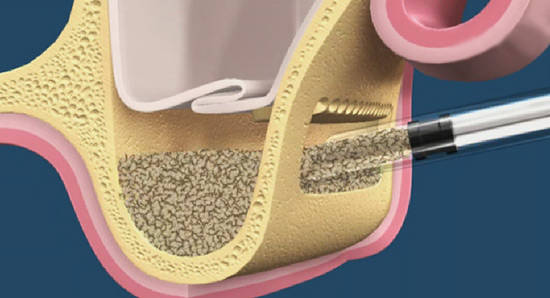

О том, почему открытый синуслифтинг безопаснее закрытого. И почему при закрытом синуслифтинге я не рекомендую использовать биоматериалы:

Каковы показания к открытому синуслифтингу? Когда его можно проводить совместно с установкой имплантов. а когда лучше сделать отдельным этапом?

Как правильно и аккуратно сделать доступ в верхнечелюстную полость? И как создать достаточное по объёму субантральное пространство?

Как выбрать графт для заполнения субантрального пространства? И на какие свойства графта нужно обратить максимум внимания?

Что делать, если вдруг случилась перфорация слизистой оболочки?

Как реабилитировать пациента после операции синуслифтинга и как минимизировать риск возможных осложнений?